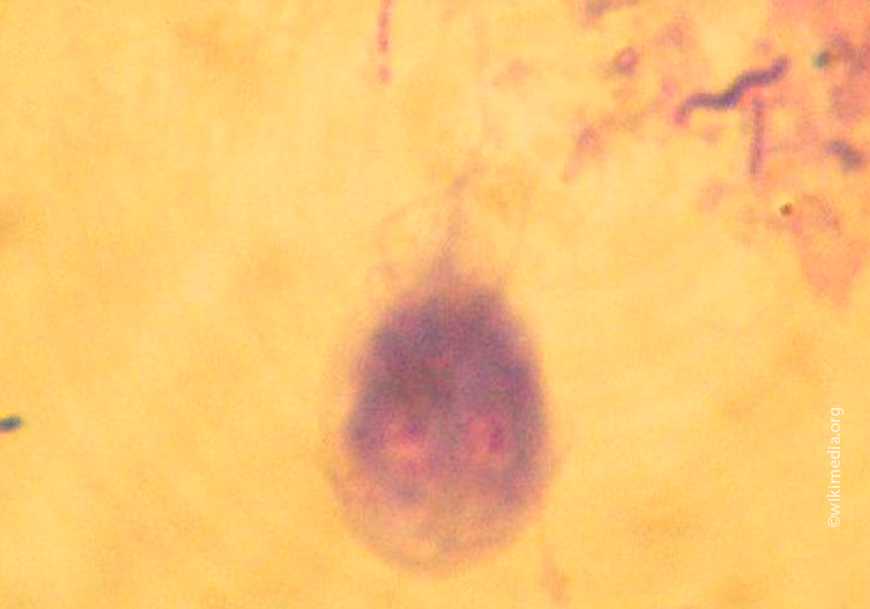

Простейшее вида Lamblia существует в двух морфологических формах. В подвижной вегетативной форме (трофозоиты) паразит живет в благоприятных условиях, то есть в кишечнике собаки; «законсервированную» форму (цисты) лямблия приобретает, попадая в неблагоприятную наружную среду.

Трофозоиты имеют грушевидную форму, содержат 2 ядра, 4 пары жгутиков, которые служат органами движения, и диск, с помощью которого они закрепляются на эпителии кишки. Размеры трофозоитов составляют примерно 9х12 мкм. Цисты лямблий имеют такие же размеры, но овальную форму, жгутиковый аппарат у них свернут.

Лямблия – одноклеточный жгутиковый паразит, существует в двух формах – трофозоит (вегетативная) и циста. Интенсивность поражения кишечника объясняется быстрым парным делением клетки, одна она делится за 15-20 минут.

Лямблии (гиардии) находятся в организме в двух формах — трофозоиты и цисты.

Трофозоиты

Это одноклеточные подвижные микроорганизмы, которые находясь внутри животного проникают в желудочно-кишечный тракт и присасываются к стенкам тонкого кишечника.

В этом и заключается их патогенное (вредное) воздействие. Они не нарушают целостность кишечника, но когда их много, они буквально облепляют тонкую кишку изнутри. Нарушается всасываемость питательных веществ.

Цисты

Это временная, неподвижная форма паразита. Простыми словами — это капсула, покрытая очень прочной и устойчивой оболочкой, внутри которой находится два Трофозоита.

В форме цисты лямблии оказываются во внешней среде, покидая организм вместе с фекалиями. От воздействия факторов внешней среды лямблии надежно защищены оболочкой цисты, пока не попадает в организм нового хозяина.